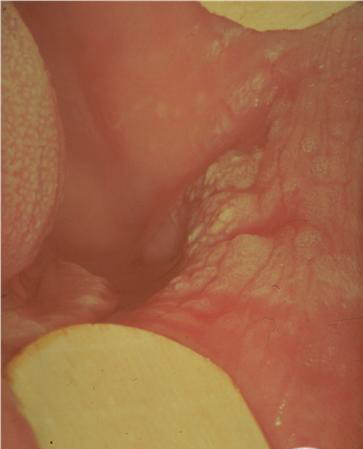

Leucoplakia Praecancerosa = الطلاوة ماقبل السرطانية